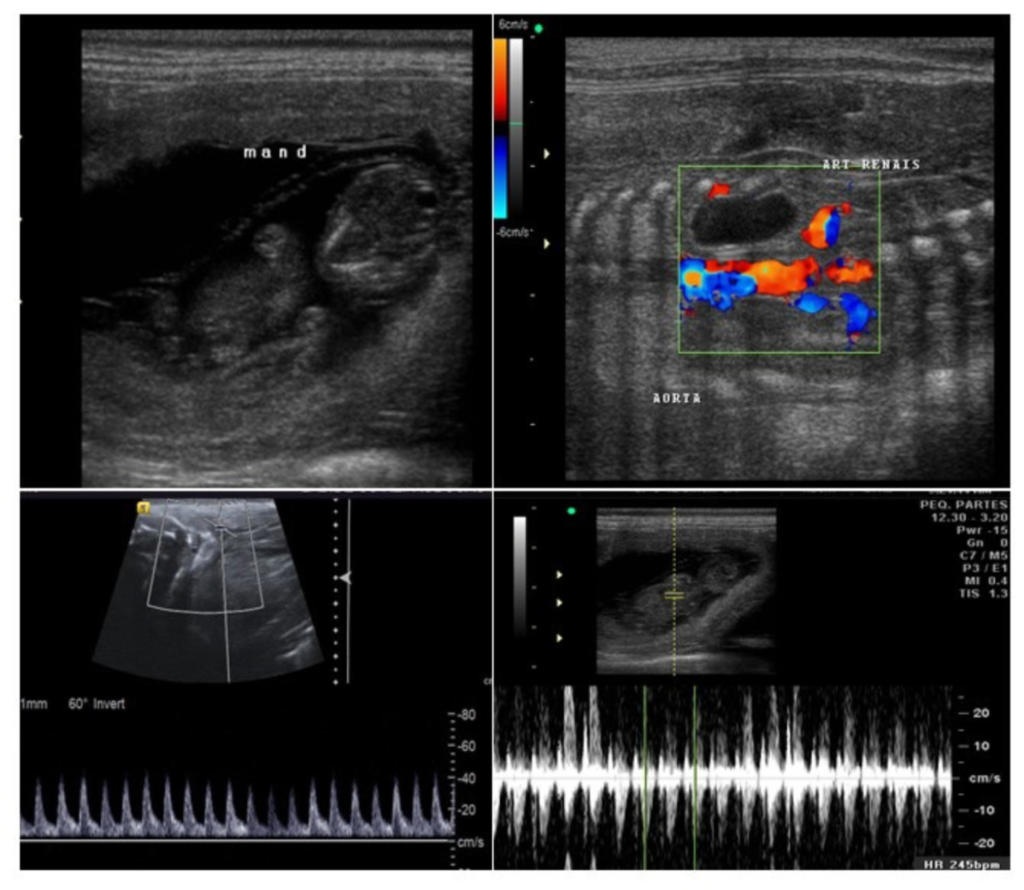

Novo exame disponível de ultrassonografia pré-natal para cadelas e gatas

O Setor de Imagem do HVU iniciou a realização de exames externos de ultrassonografia gestacional em cadelas e gatas. Os exames ocorrem às quartas-feiras, das 8h 30min às 11h, conforme disponibilidade de agendamento.

Imagem cedida pelo Setor de Imagem do HVU